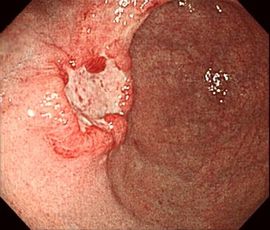

[胃がん] 手術:腹腔鏡下胃全摘術

内視鏡画像